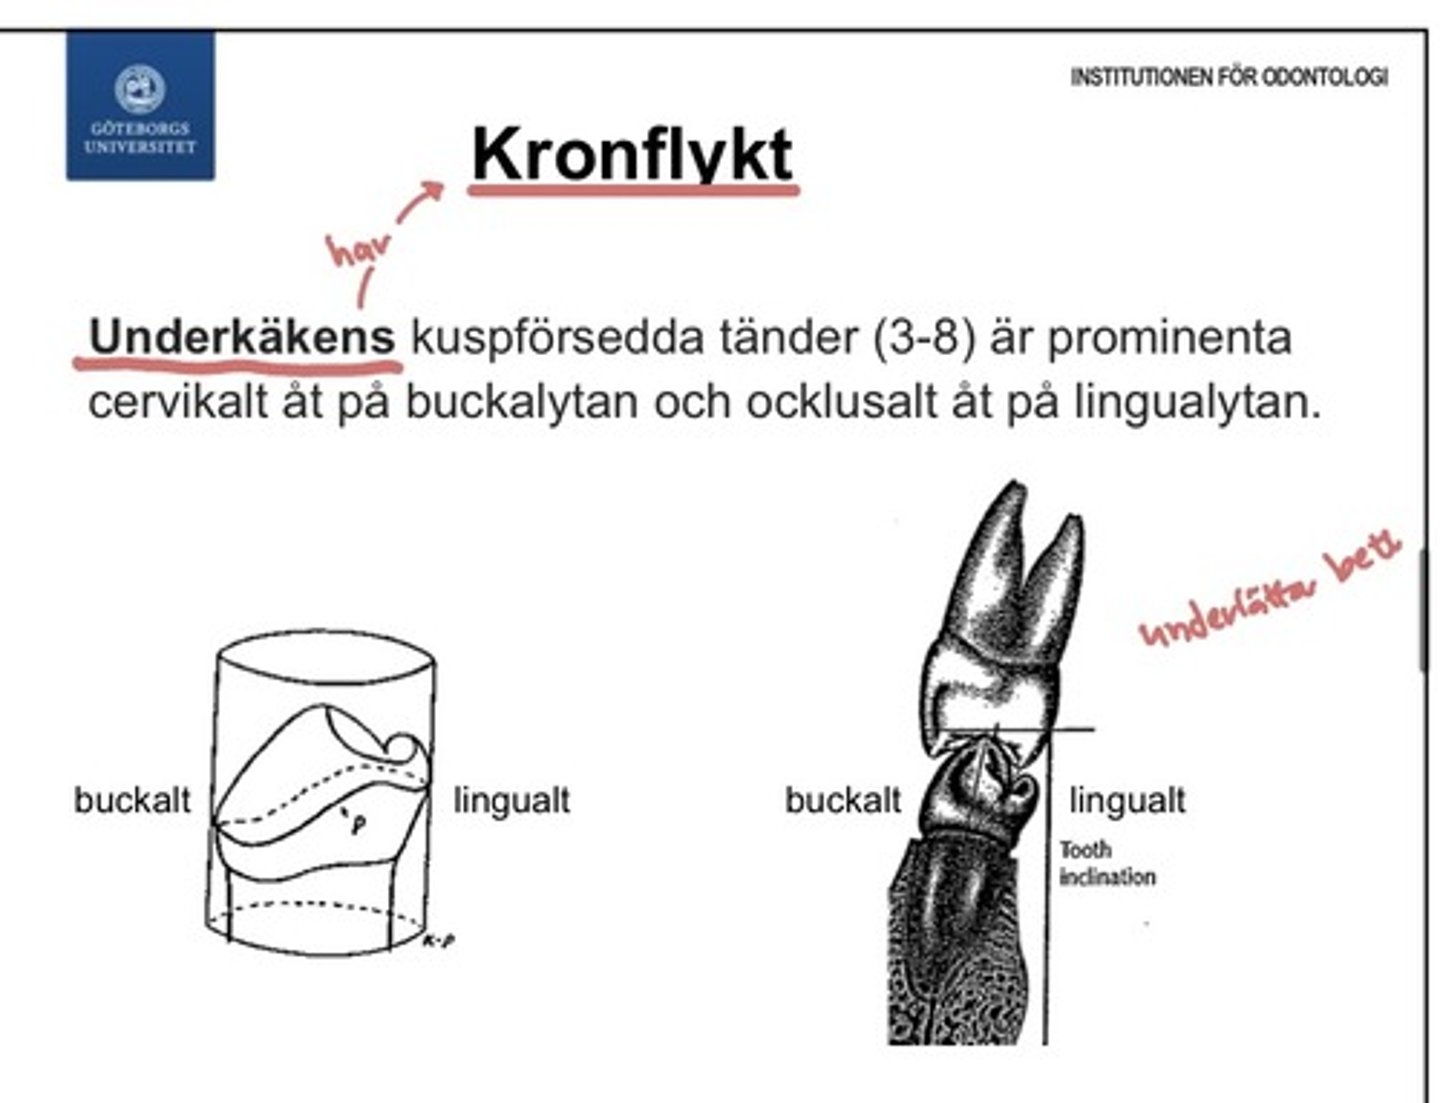

kronflykt

Undekäkens kuspförsedda tänder (3-8) är prominenta

- cervikalt åt på buckal ytan

- ockusalt åt på lingualytan

Prominenslinjen hos de kuspförsedda tänderna i mandibeln är inte mitt på tanden (som för motsvarande tänderna i maxillan).

Detta innebär att tandkronan lutar inåt vilket är viktigt för att man ska kunna bita ihop ordentligt, och är således också viktigt för tuggningsförmågan.